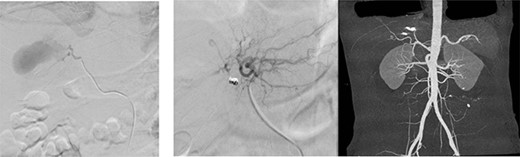

Embolization was achieved using gel foam and particle (embosphere: 100–300 mic) through microcatheter until satisfactory stagnation of forward flow was reached and back flow was seen. Then, the aneurysm was occluded with placement of six microcoils (3 and 5 mm) (Fig. 6).

(a) Arteriogram showing a hepatic artery pseudoaneurysm in the right hepatic artery; (b) shows post-embolization selective arteriogram showing disappearance of the pseudoaneurysm in the right lobe of the liver; CT angiogram shows successful embolization (c).

After 1 week of embolization, a follow-up CT scan detected thrombosis of the lateral segmental branch of the left portal vein. Prophylaxis dose of heparin was increased to the therapeutic range and, a week later, duplex US examination was performed, which documented the resolution of this thrombosis. The patient was transferred to the rehabilitation care on daily oral aspirin. A repeat CT scan was done after 1 month in which no pseudoaneurysm was seen, with normal flow in the hepatic arteries and portal vein (Fig. 7). During the following 2 months, the patient remained asymptomatic and was discharged home without complications.

Repeated CT scan of the abdomen after 4 weeks revealed partial healing of the liver injury with disappearance of the pseudoaneurysm.